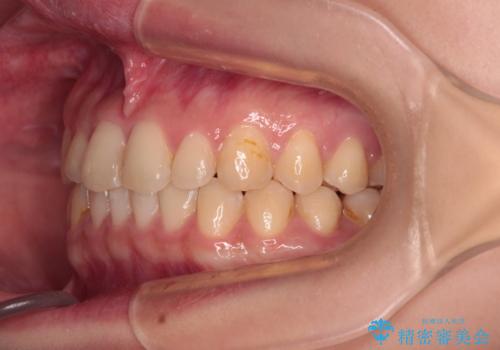

治療途中の奥歯と矯正治療の後戻り インビザライン・ライトによる矯正治療

- 根管治療を行ったままの奥歯と、矯正治療の後戻りを気にして来院された患者様です。

根管治療された歯に症状はなく、オールセラミッククラウンにて補綴治療を行うこととしました。

矯正治療の後戻りは軽微であったため、インビザラインの簡易パッケージであるインビザライン・ライトを用いて歯列を整えることとしました。

クラウンはよりよい咬み合わせで装着したいため、インビザラインを1セット使用して概ね歯列を整えた時点で補綴治療を行い、その後仕上げの矯正治療を行いました。